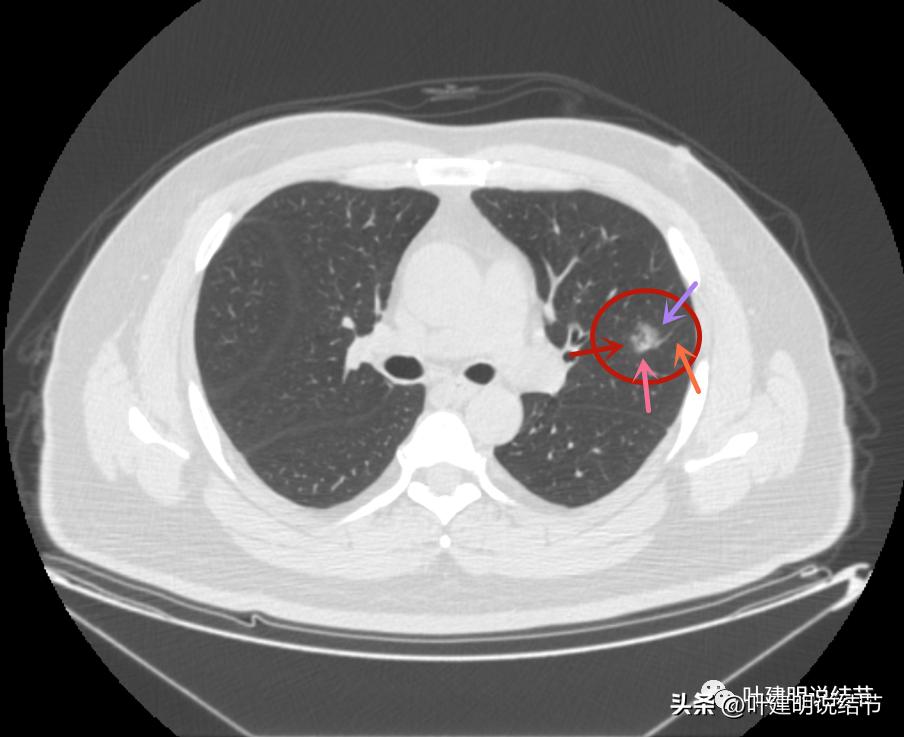

左上病灶2与左上病灶3:

病灶2出现,还只有一点点磨玻璃影,血管走行有点异样

密度略显高,有微血管进入(桔色箭头),边缘略模糊,但轮廓还是较清

中间有实性成分出现(粉色箭头),微血管进入明显(桔色箭头),边上有磨玻璃成分(绿色箭头),整体轮廓清

边上另有病灶出现,即左上病灶3(蓝色箭头)

病灶3也有微血管进入(桔色箭头)

病灶3密度不均,轮廓清,有细毛刺样征(紫色箭头)

毛刺征(紫色箭头),微血管征(桔色箭头),实性点状成分(粉色箭头),整体轮廓较清(红色箭头)